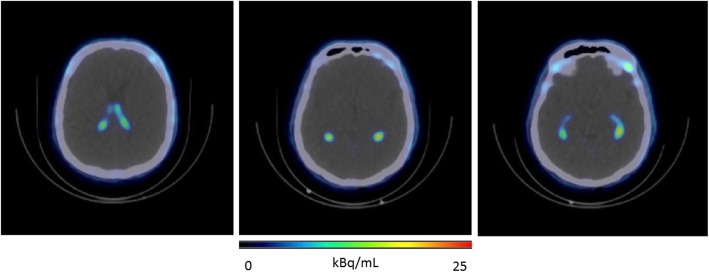

Fig. 2.

Typical 18F-AzaFol uptake pattern in the choroid plexuses (lateral ventricles) for a representative patient at 30 min post-administration

A typical biodistribution of 18F-AzaFol is shown in Fig. 1 (MIP images at 60 min for the six patents are shown in Figure S4 of Supplemental Data 4). The main way of biological excretion of the radiopharmaceutical from the body was through the urine. Prominent kidney uptake was visible in the early phase followed by rapid renal wash-out. Significant urinary bladder activity accumulation was seen as early as 10 min after injection. A significant uptake was observed in the choroid plexuses from the early time point images (Fig. 2).

Specific biological uptake was found in the choroid plexuses. This small vascular structure was segmented by emission-based threshold segmentation to avoid important PET signal spill-out. We adopted a threshold of 5% of the maximum signal intensity to delineate the choroids VOI. This relatively low threshold level was possible considering the negligible tracer uptake of the surrounding cerebral tissue. An example of source organ VOI segmentation is provided in Supplemental Data 1 (Figure S1).